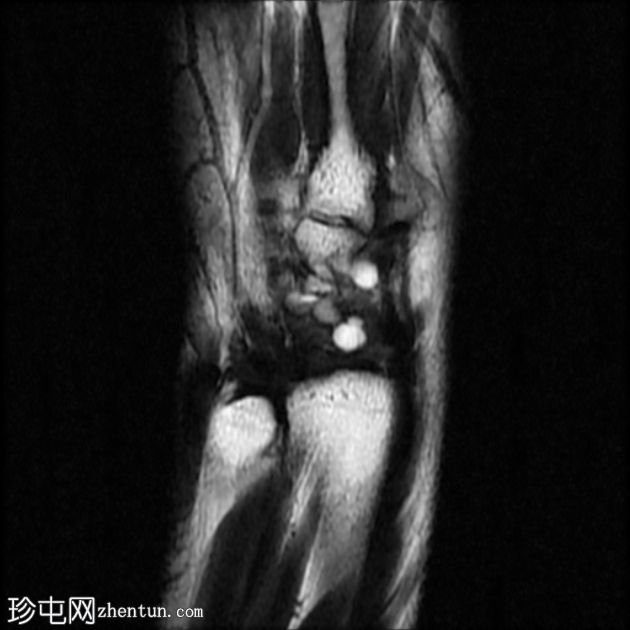

MRI

STIR序列

冠状位

腕背多房性腱鞘囊肿(轴位、矢状位和冠状位图像均可见),位于伸肌腱下方的腕背关节囊内,提示为腕背腱鞘囊肿。

该病例展现了腕背腱鞘囊肿的典型

影像

学表现和位置。